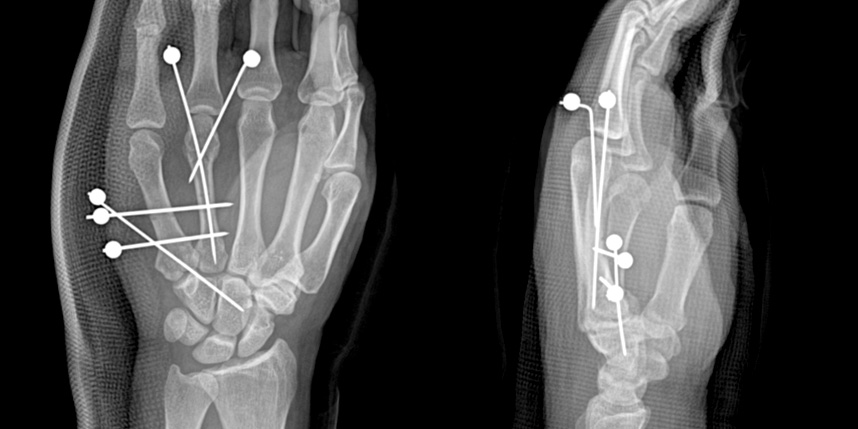

손가락 골절